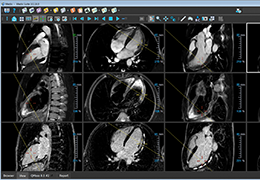

ANYTHINK 经导管主动脉瓣膜置换术分析系统